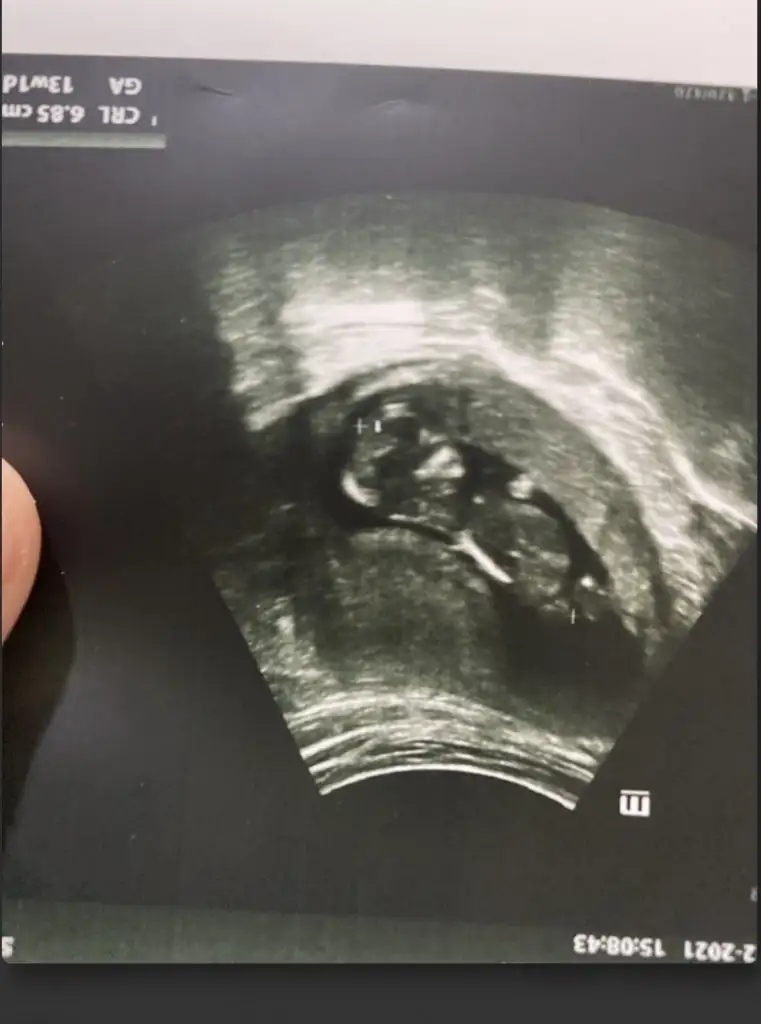

Ikra meyra merhaba 12+2 haftalık. Bakabilir misin.

Şimdiden teşekkürler

• IMG_20220108_134149.webp

17,6 KB · Görüntüleme: 64

• IMG_20220108_134129.webp

21,5 KB · Görüntüleme: 65

• IMG_20220108_134106.webp

22 KB · Görüntüleme: 67